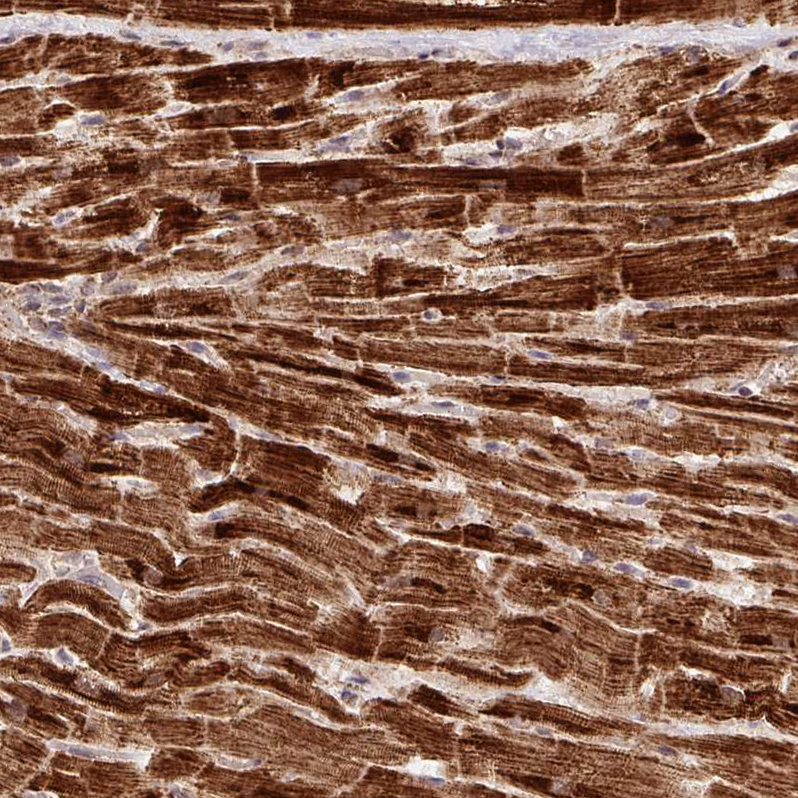

Immunohistochemical staining of human fallopian tube, gastrointestinal, heart muscle and kidney using Anti-ATP5A1 antibody HPA040622 (A) shows similar protein distribution across tissues to independent antibody HPA044202 (B).